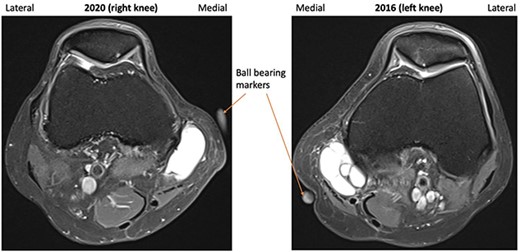

A repeat MRI was performed and reported ‘very similar’ appearances to the left knee, showing a septated ganglion originating from the postero-medial aspect of the joint and subchondral cyst formation with a pattern and location mirroring that which had involved the left knee (Figs 1–3). Reassured by these findings, the patient deferred surgery.

2016 and 2020 T2-weighted MRI in transverse plane with ganglion cyst visible medially.